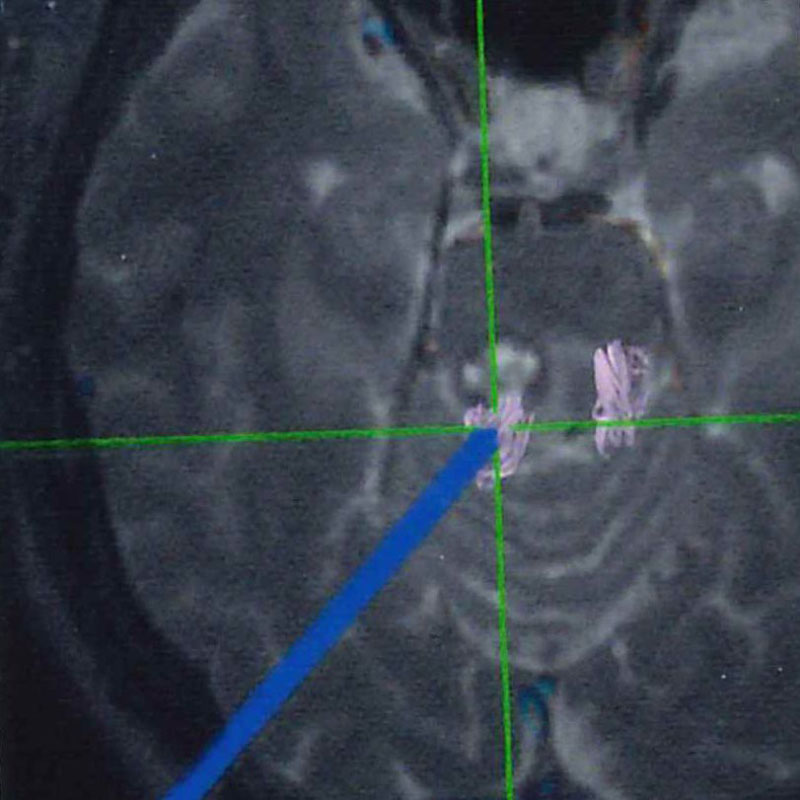

'25年1月

50代

南田,野本

右小脳

出血性海綿状血管腫

再出血の予防目的

兵庫県の病院

より紹介

No.No.59 手術前1

No.No.59 手術前2

No.No.59 手術後1

No.No.59 手術後2

CT/MRにより完全に摘出されたことが確認された